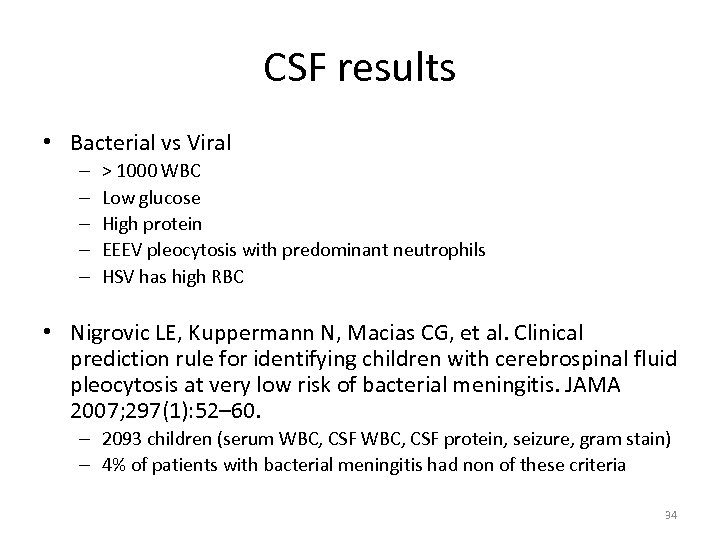

CSF results • Bacterial vs Viral – – – > 1000 WBC Low glucose High protein EEEV pleocytosis with predominant neutrophils HSV has high RBC • Nigrovic LE, Kuppermann N, Macias CG, et al. Clinical prediction rule for identifying children with cerebrospinal fluid pleocytosis at very low risk of bacterial meningitis. JAMA 2007; 297(1): 52– 60. – 2093 children (serum WBC, CSF protein, seizure, gram stain) – 4% of patients with bacterial meningitis had non of these criteria 34